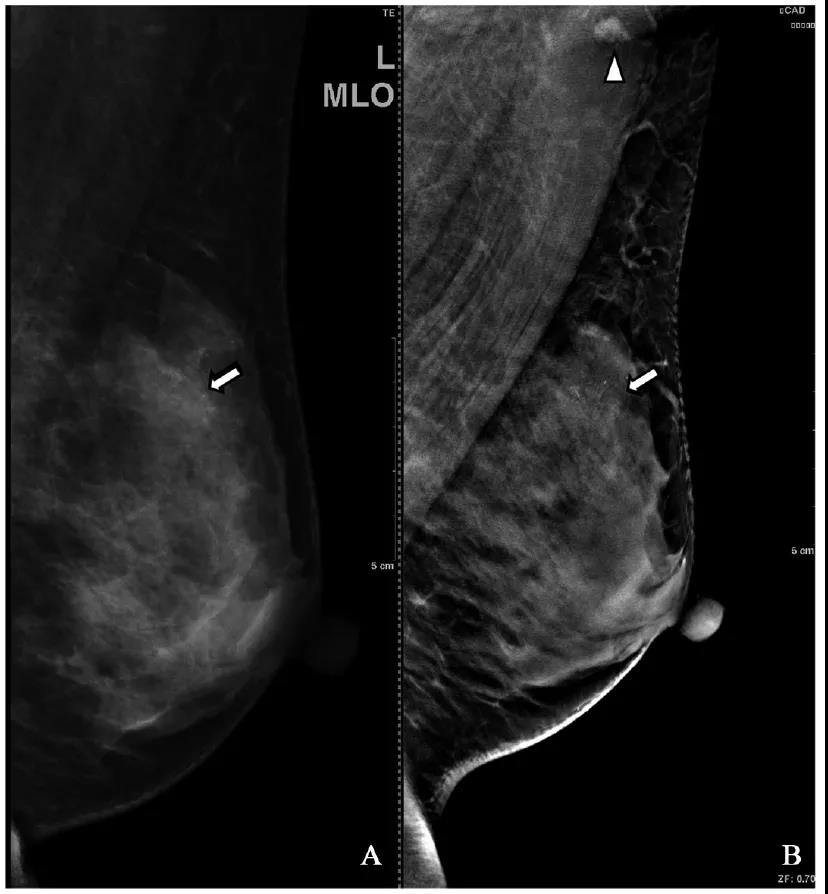

不同检查方法对67个乳腺病灶的BI-RADS分类结果见表1。其中3例微钙化病变,超声未检出,DBT显示优于FFDM(图1)。

图1 FFDM、DBT显示同一病变对比图像

注:患者,女性,55,发现右乳肿物2个月。乳腺超声:左乳多发囊肿左乳实性结节,BI-RADS 3。A:FFDM左乳外上象限局部腺体密度增高,其内成簇多形性微钙化(箭头所示),BIRADS 4C。B:DBT同一病变区域成簇微钙化形态分布较FFDM清晰。腋窝淋巴结(三角形所示)形态较FFDM显示清晰。